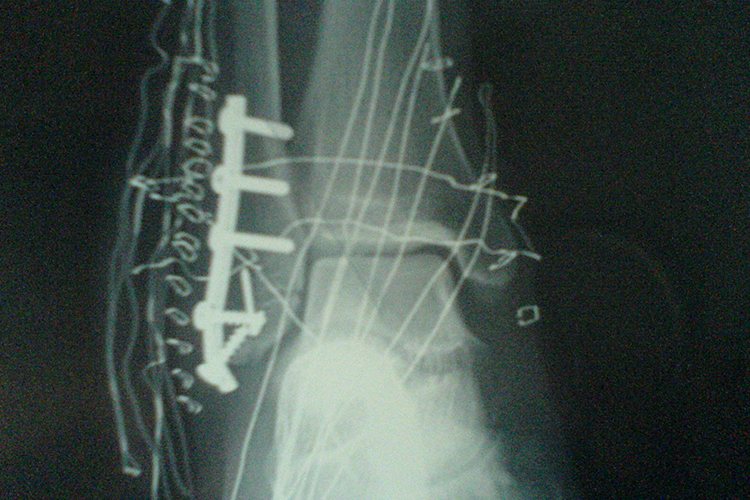

Ⅱ型骨折即三踝骨折,内踝骨折采用松质骨螺钉内固定,外踝骨折常采用钢板固定。影响胫骨1/4-1/3关节面的后踝骨折也需用松质骨螺钉或支撑钢板内固定。

Ⅲ型骨折除了需要对内踝行切开复位、内固定外,外踝或腓骨骨折也应行钢板螺钉内固定,固定腓骨是保证胫腓下端稳定性的重要方法。